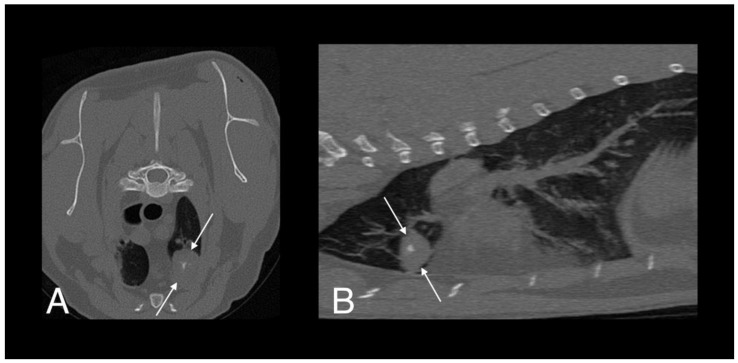

The patient re-presented one month later for continued tail chewing and no improvement on gabapentin and meloxicam. Hematology was unremarkable, while creatinine (270 umol/L; reference interval [R1] 40–177) and urea (23.6 mmol/L; RI 2.8–9.8) were increased on serum biochemical analysis. Magnetic resonance imaging (MRI) of the lumbosacral spine and caudal vertebrae demonstrated a large, expansile, heterogeneous, and strongly contrast-enhancing soft tissue lesion originating from the right sacroiliac joint. The mass was extending into the psoas musculature and causing osteolysis of the sacrum (Figure 2). A second heterogeneous soft tissue mass was identified in the ventral aspect of the tail base. This lesion was invading the hypaxial coccygeal muscles and causing mild osteolysis of the haemal arches of the coccygeal vertebrae (Figure 3). The regional lymph nodes were mildly enlarged. Whole body computed tomography (CT) was performed to further assess the osteolysis and for staging purposes. This confirmed the MRI findings affecting the tail and sacroiliac joint, but also found a large, round, partially mineralized soft tissue mass within the ventral portion of the left cranial lung lobe (Figure 4).

Figure 4.

Computed tomography (CT) images of cat 1 in transverse (A) and sagittal (B) planes showing a well-defined pulmonary mass with central mineralization (arrows).

Four months later, a repeat CT scan was performed. The lesion within the left cranial lung lobe had decreased moderately in size (Figure 6A). The osteolytic lesions had almost completely healed, leaving only a mildly irregular margin of the right sacroiliac joint surface. The soft tissue mass at the tail base was no longer visible and the regional lymphadenopathy had resolved (Figure 6B). Hematology revealed leukopenia (5.2 × 109/L; RI 7.0–20.0) with mild neutropenia (2.13 × 109/L; RI 2.5–12.8). Serum biochemistry revealed mildly increased urea (16.9 mmol/L; RI 2.8–9.8) but was otherwise unremarkable. Echocardiographic changes were static from the previous findings five months prior.

Figure 6.

Follow up CT scan images of the lung (A) and sacroiliac joints (B) of cat 1, four months after starting antimycobacterial treatment. The lesion within the left cranial lung lobe is still visible but had moderately decreased in size (arrows). The osteolytic lesions of the right sacroiliac joint are subtle, with a mildly irregular margin of the joint surface (arrows). The soft tissue mass at the tail base is no longer present.

A total of eight months after initiating antimicrobial therapy, a final CT was performed. The pulmonary nodule was static in size and appearance, there was no evidence of soft tissue mass recurrence and no new lesions were identified. Antimicrobial therapy was discontinued, and no clinical signs consistent with recrudescence or recurrence of infection have been observed during two and a half years of follow-up.